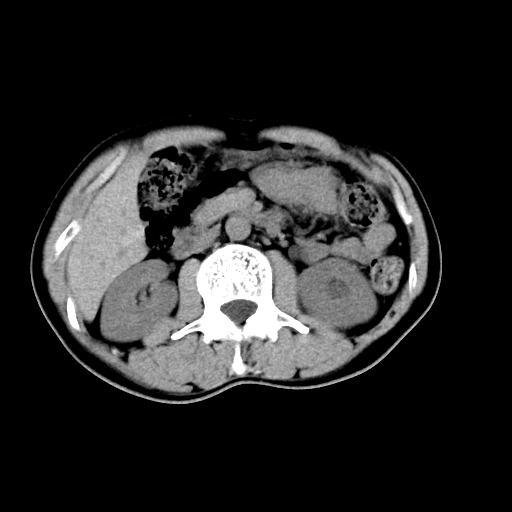

男,47岁,左输尿管结石碎石治疗后10余日。彩超示:左输尿管下段狭窄、输尿管积水。请各位讨论一下左输尿管下段结石还是静脉石?

两侧髂总动脉壁斑状及点状钙化.左侧输尿管行经与左髂总动脉相交后见高密度影,且下段输尿管管腔未见扩张,应该要考虑结石伴以上输尿管及肾盂积水.但右侧结节状高密度影,也应该是结石吧!那以上输尿管未见扩张呢!因此静脉结石可能性也较大.请问楼主碎石前左侧输尿管结石位置.

虽左侧有轻度肾盂积水但不支持结石。1结石边周应该有软组织包绕呈晕征。2钙化点前面见输尿管影也不支持是结石。3彩超没提结石。建议超生复查。

输尿管先位于腹部,后进入盆腔,最后斜穿膀胱壁开口于膀胱,因此,临床上常将输尿管分为腹段、盆段和壁内段。第1个狭窄:在肾盂与输尿管移行处。第2个狭窄:在跨过髂血管处。第3个狭窄:在穿过膀胱壁处。这些狭窄是结石容易滞留的部位。

同意,不支持结石。(因显示该高密度影前见扩张输尿管影,另外两侧对称显示)。

左侧高密度影在左侧输尿管的内侧方,所以不考虑输尿管结石.

我认为不是结石的可能性大,因为他的位置和血管钙化的位置邻近